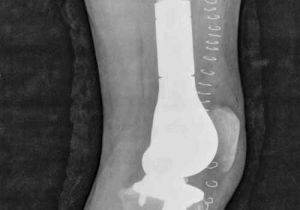

मासूम के दाएं पैर में घुटने के ऊपर था कैंसर, डॉक्टरों ने मेगा प्रोस्थेसिस लिम्ब सॉल्वेज सर्जरी कर पैर कटने से बचाया

6 May, 2023 12:01 PM IST | SAMWADINDIA.INरायपुर हाल ही में डॉ. भीमराव अम्बेडकर स्मृति चिकित्सालय के अस्थि रोग विभाग में डॉक्टरों की...